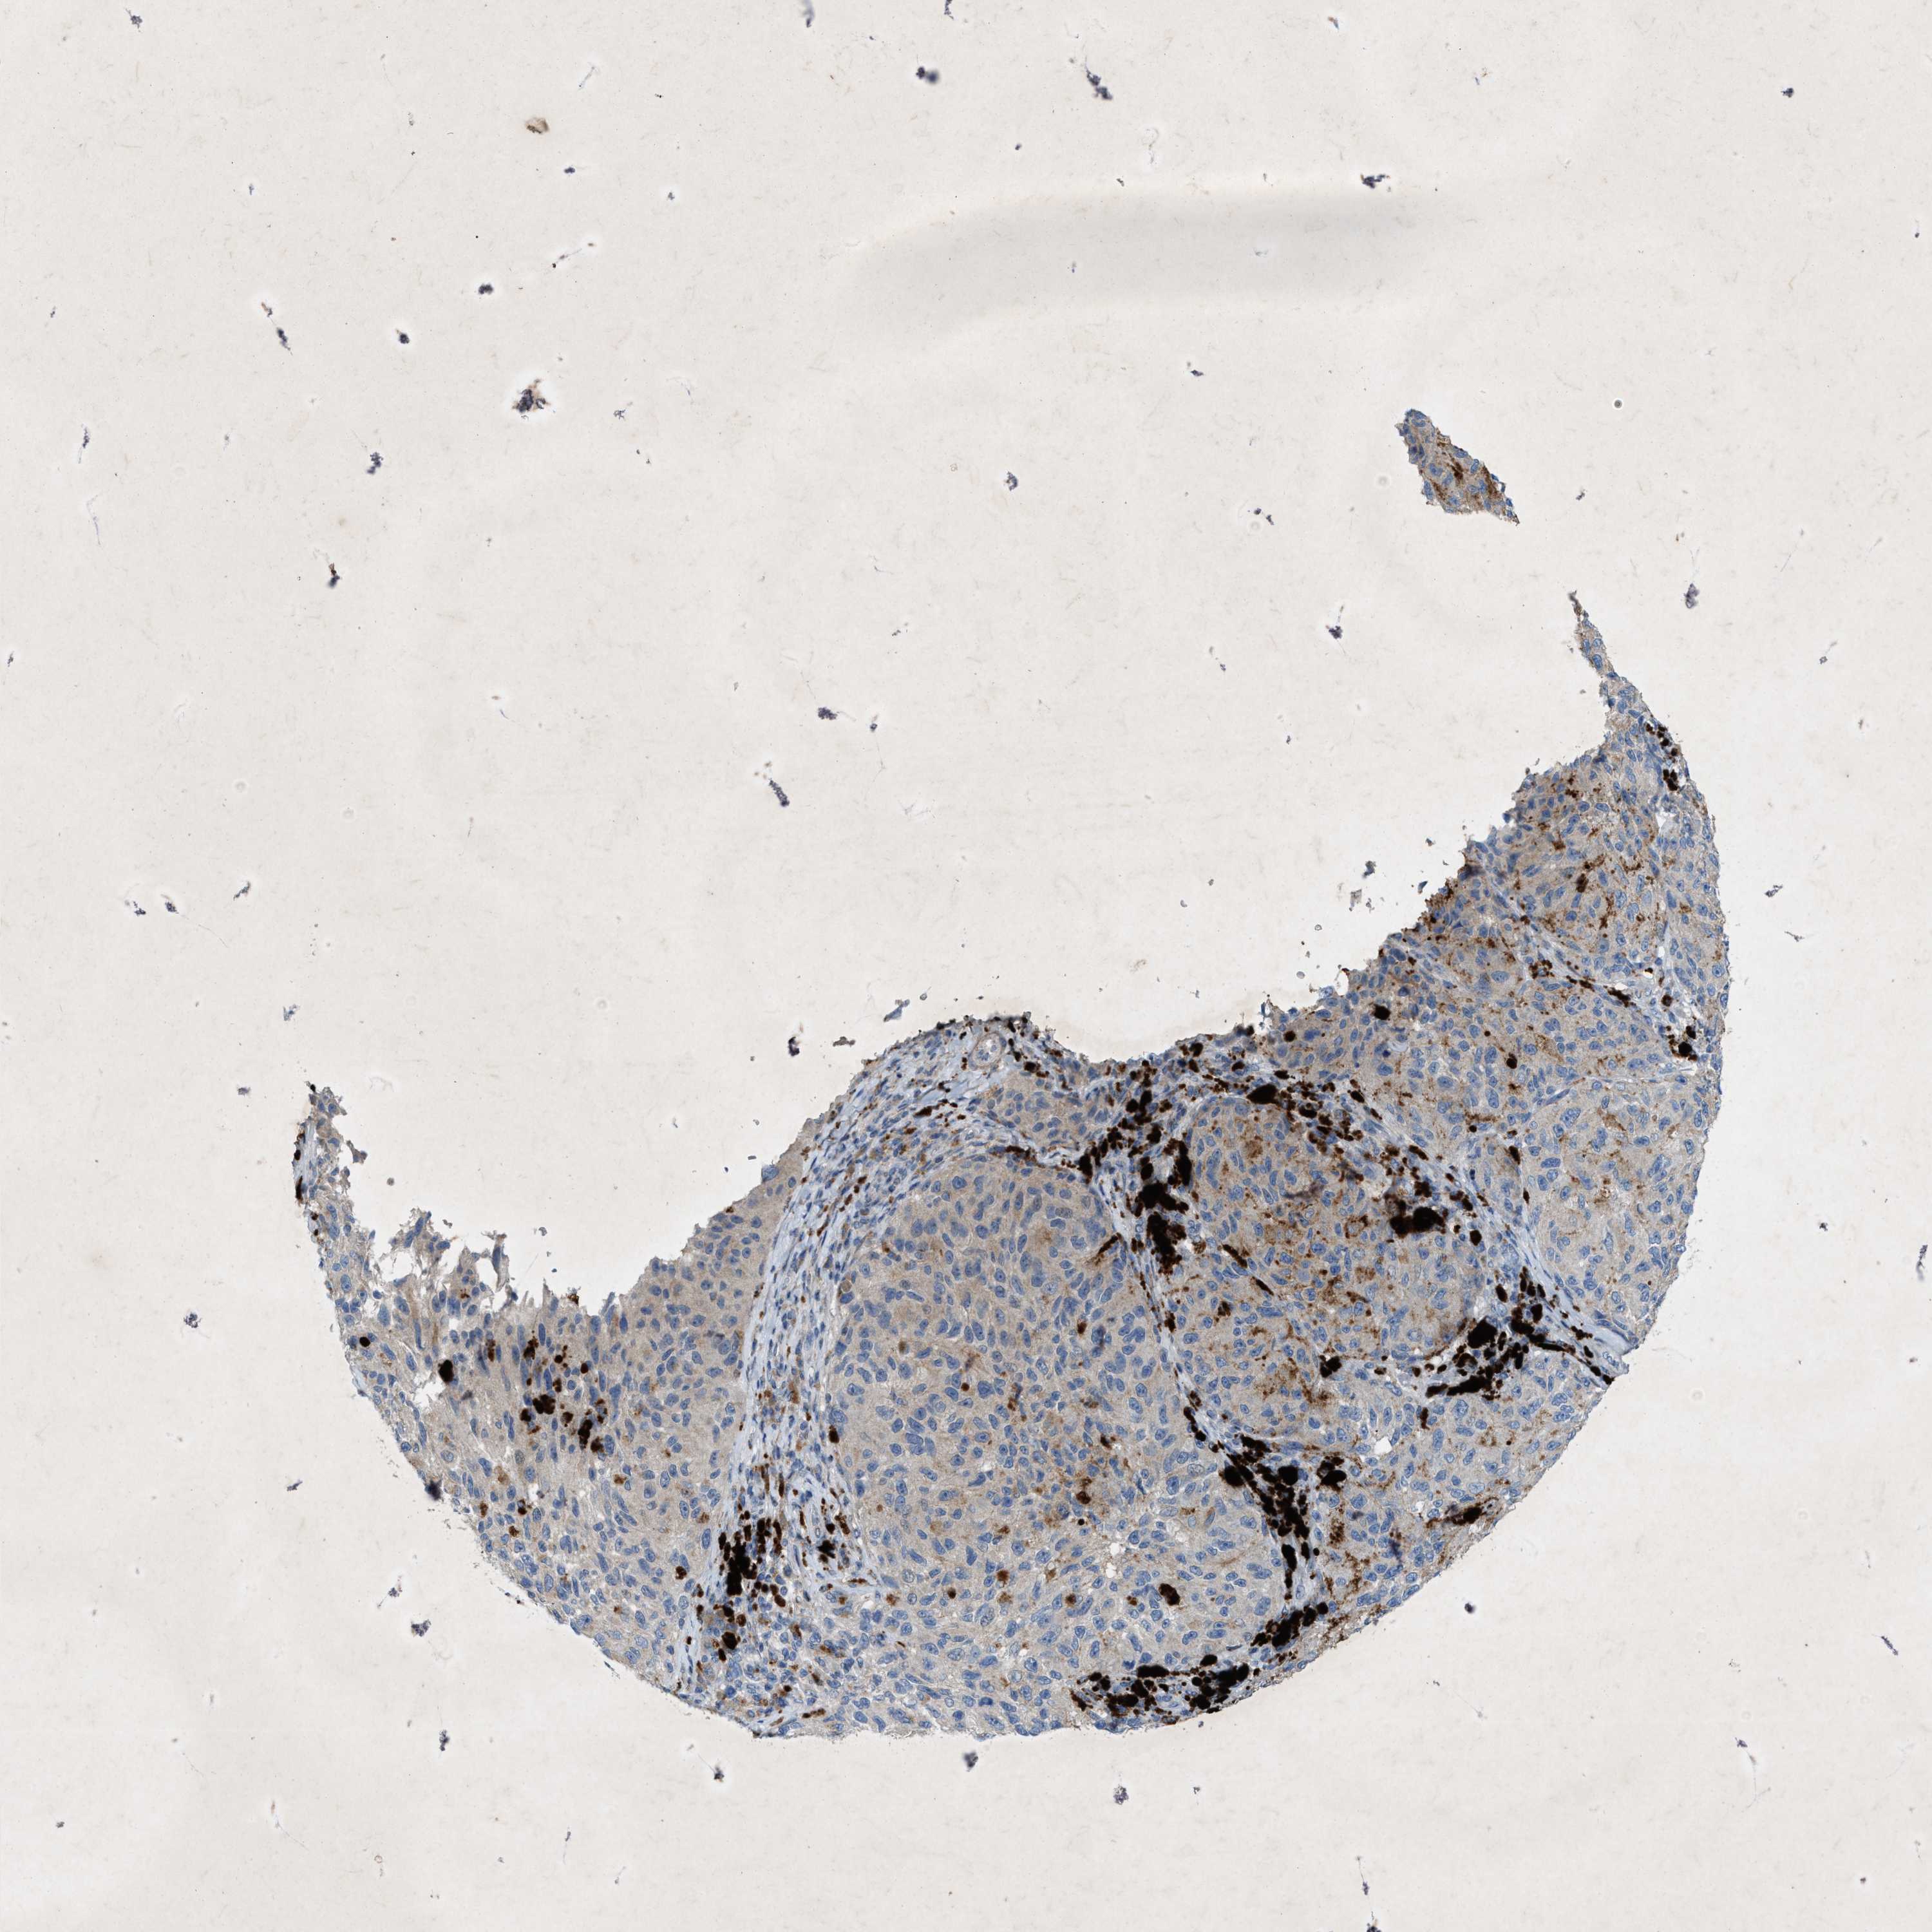

MELANOMA - Protein expressioni

A mouse-over function shows sample information and annotation data. Click on an image to view it in a full screen mode. Samples can be filtered based on level of antibody staining by selecting one or several of the following categories: high, medium, low and not detected. The assay and annotation is described here.

Note that samples used for immunohistochemistry by the Human Protein Atlas do not correspond to samples in the TCGA dataset.

Antibody stainingi

Antibody staining in the annotated cell types in the current human tissue is reported as not detected, low, medium, or high, based on conventional immunohistochemistry profiling in selected tissues. This score is based on the combination of the staining intensity and fraction of stained cells.

Each image is clickable and will lead to virtual microscopy that enables deeper exploration of all samples and also displays staining intensity scores, fraction scores and subcellular localization as well as patient and tissue information for each sample.

Antibody HPA019879

Antibody HPA020134

Antibody HPA029468

Staining

High

Medium

Low

Not detected

Intensity

Strong

Moderate

Weak

Negative

Quantity

>75%

75%-25%

<25%

None

Location

Nuclear

Cytoplasmic/membranous

Cytoplasmic/membranous,nuclear

Malignant melanoma, NOS

Malignant melanoma, Metastatic site